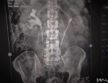

A ma délután bemutatott műszer még pontosabb, jobb minőségű felvételek készítésére alkalmas, ráadásul mindezt csökkentett sugárdózis alkalmazásával teszi, és rövidebb idő alatt elődeinél. Ennek köszönhetően nő a napi ellátott betegszám, vagyis csökken a röntgen-vizsgálatra való várakozási idő.

Dr. Szántó Árpád, a pécsi Urológiai Klinika igazgató-főorvosa a beruházás kapcsán elmondta: Az új eszköz lehetővé teszi a gyorsabb, pontosabb, jobb minőségű felvételek készítését csökkentett sugárdózis alkalmazásával, továbbá rövidebb idő alatt végezhetőek el a vizsgálatok, ebből következően nő a napi ellátott betegszám, és csökken a várakozás időtartama. A napi rutin mellett a kórházi ellátáshoz kapcsolódó egyéb röntgen vizsgálatok elvégzése, illetve a digitális technika alkalmazásával a távleletezés is elérhetővé válik, így a frissen operált beteg nincs kitéve a más intézetbe való szállítás viszontagságainak, valamint a műtéti tervezés folyamatai is egyszerűsödnek – hangsúlyozta a klinikaigazgató.

Elhangzott, hogy a napi betegforgalom részét képező veseköves, görcsös panaszoktól szenvedő beteg, vagy egy vizelet elfolyási akadályt fenntartó kő kontrasztanyagos röntgenvizsgálattal történő pontos diagnózisának felállításában, illetve a műtétes beavatkozások gyógyultságának ellenőrzésében nagy előnyt jelent a házon belül elérhető új vizsgálati lehetőség. Az új készülékkel éves szinten mintegy 2500-3000 beteget tudnak megvizsgálni.